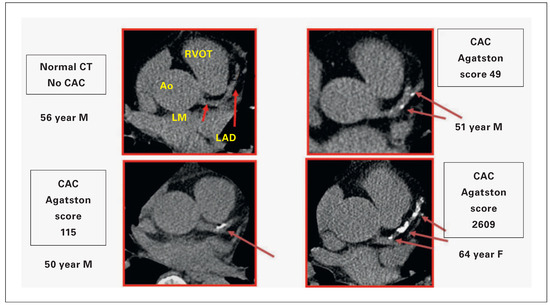

The Coronary Calcium Score for Risk Prediction

by Raimund Erbel, Amir A Mahabadi and Hagen Kälsch

Sudden cardiac death belongs to the acute coronary syndromes, beside unstable angina and myocardial infarction. Today, 60%–80% of deaths due to myocardial infarction still occur outside the hospital. In order to detect individuals prone to such events, risk scores have been developed, including the Heart Score of the European Society of Cardiology. Drawbacks of all current risk scores are, however, the exclusion of signs of atherosclerosis, the underlying aetiology of plaque rupture and erosion leading to sudden death. Computed tomography is an ideal imaging tool, which is able to detect, to localise and to quantify calcified and noncalcified plaques in coronary vessels. The amount of calcium is related to coronary and cardiovascular risk, as well as all-cause mortality. The use of calcium-score risk prediction can eliminate a big problem of the current risk factors, because the lifetime exposure to risk factors, including genetic and heritable features, has an important influence on atherosclerosis. Individual, meaning personalised, management is provided. Plaque burden indicates the degree of risk, which is what matters most. Full article

Show Figures

Figure 1